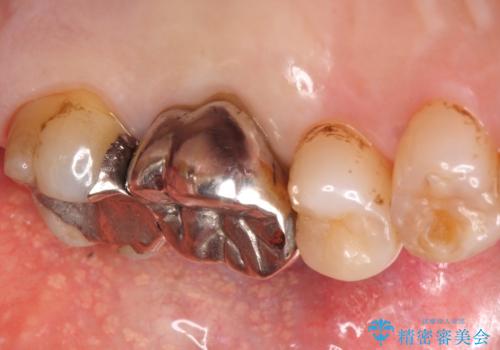

- 奥歯が咬むと痛い、熱いものがしみることを主訴に来院された患者様です。

奥歯(左上7)のメタルインレー(銀の詰め物)を除去し精査したところ、奥歯はわれていました。

根尖近くまで深くヒビが入っており保存不可能な状態でした。